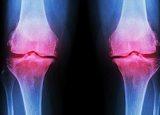

Chronische Gelenkschmerzen, z.B. Arthrose